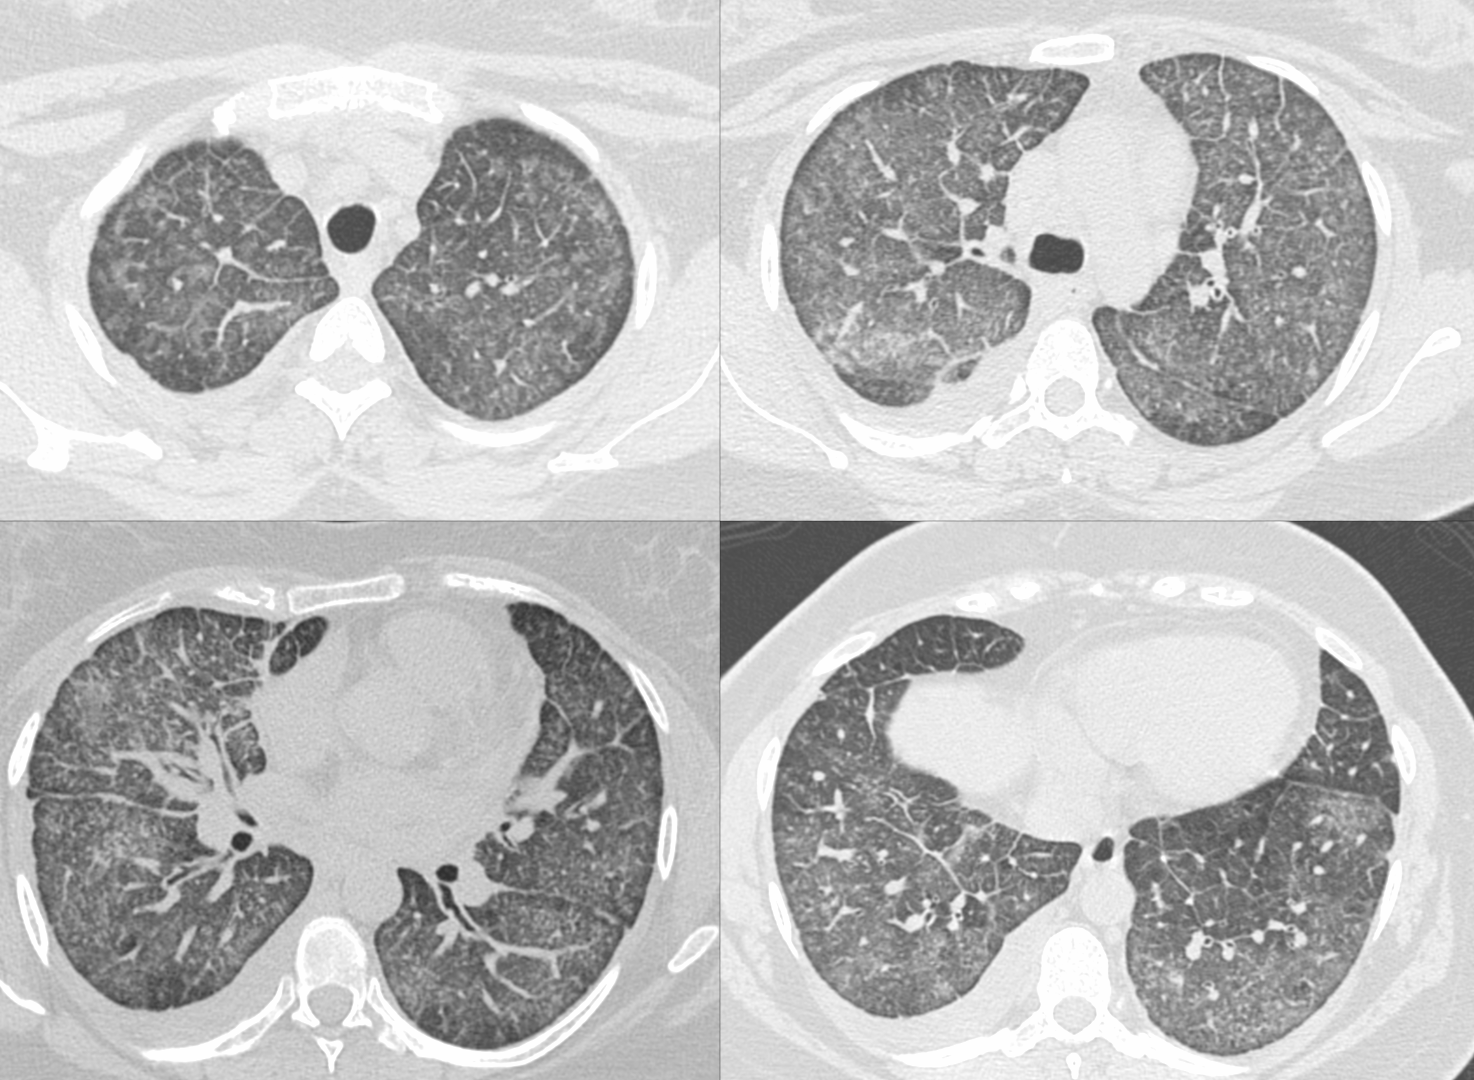

Case 115 - Ground Glass + Septal Thickening

Ground glass plus septal thickening has a specific set of conditions that can be differentiated based on appearance morphology, presentation (acute/subacute/chronic) and presence of other findings in the chest or elsewhere on whole body scanning

This 36-years old presented with gradually progressive breathlessness

What is the diagnosis?